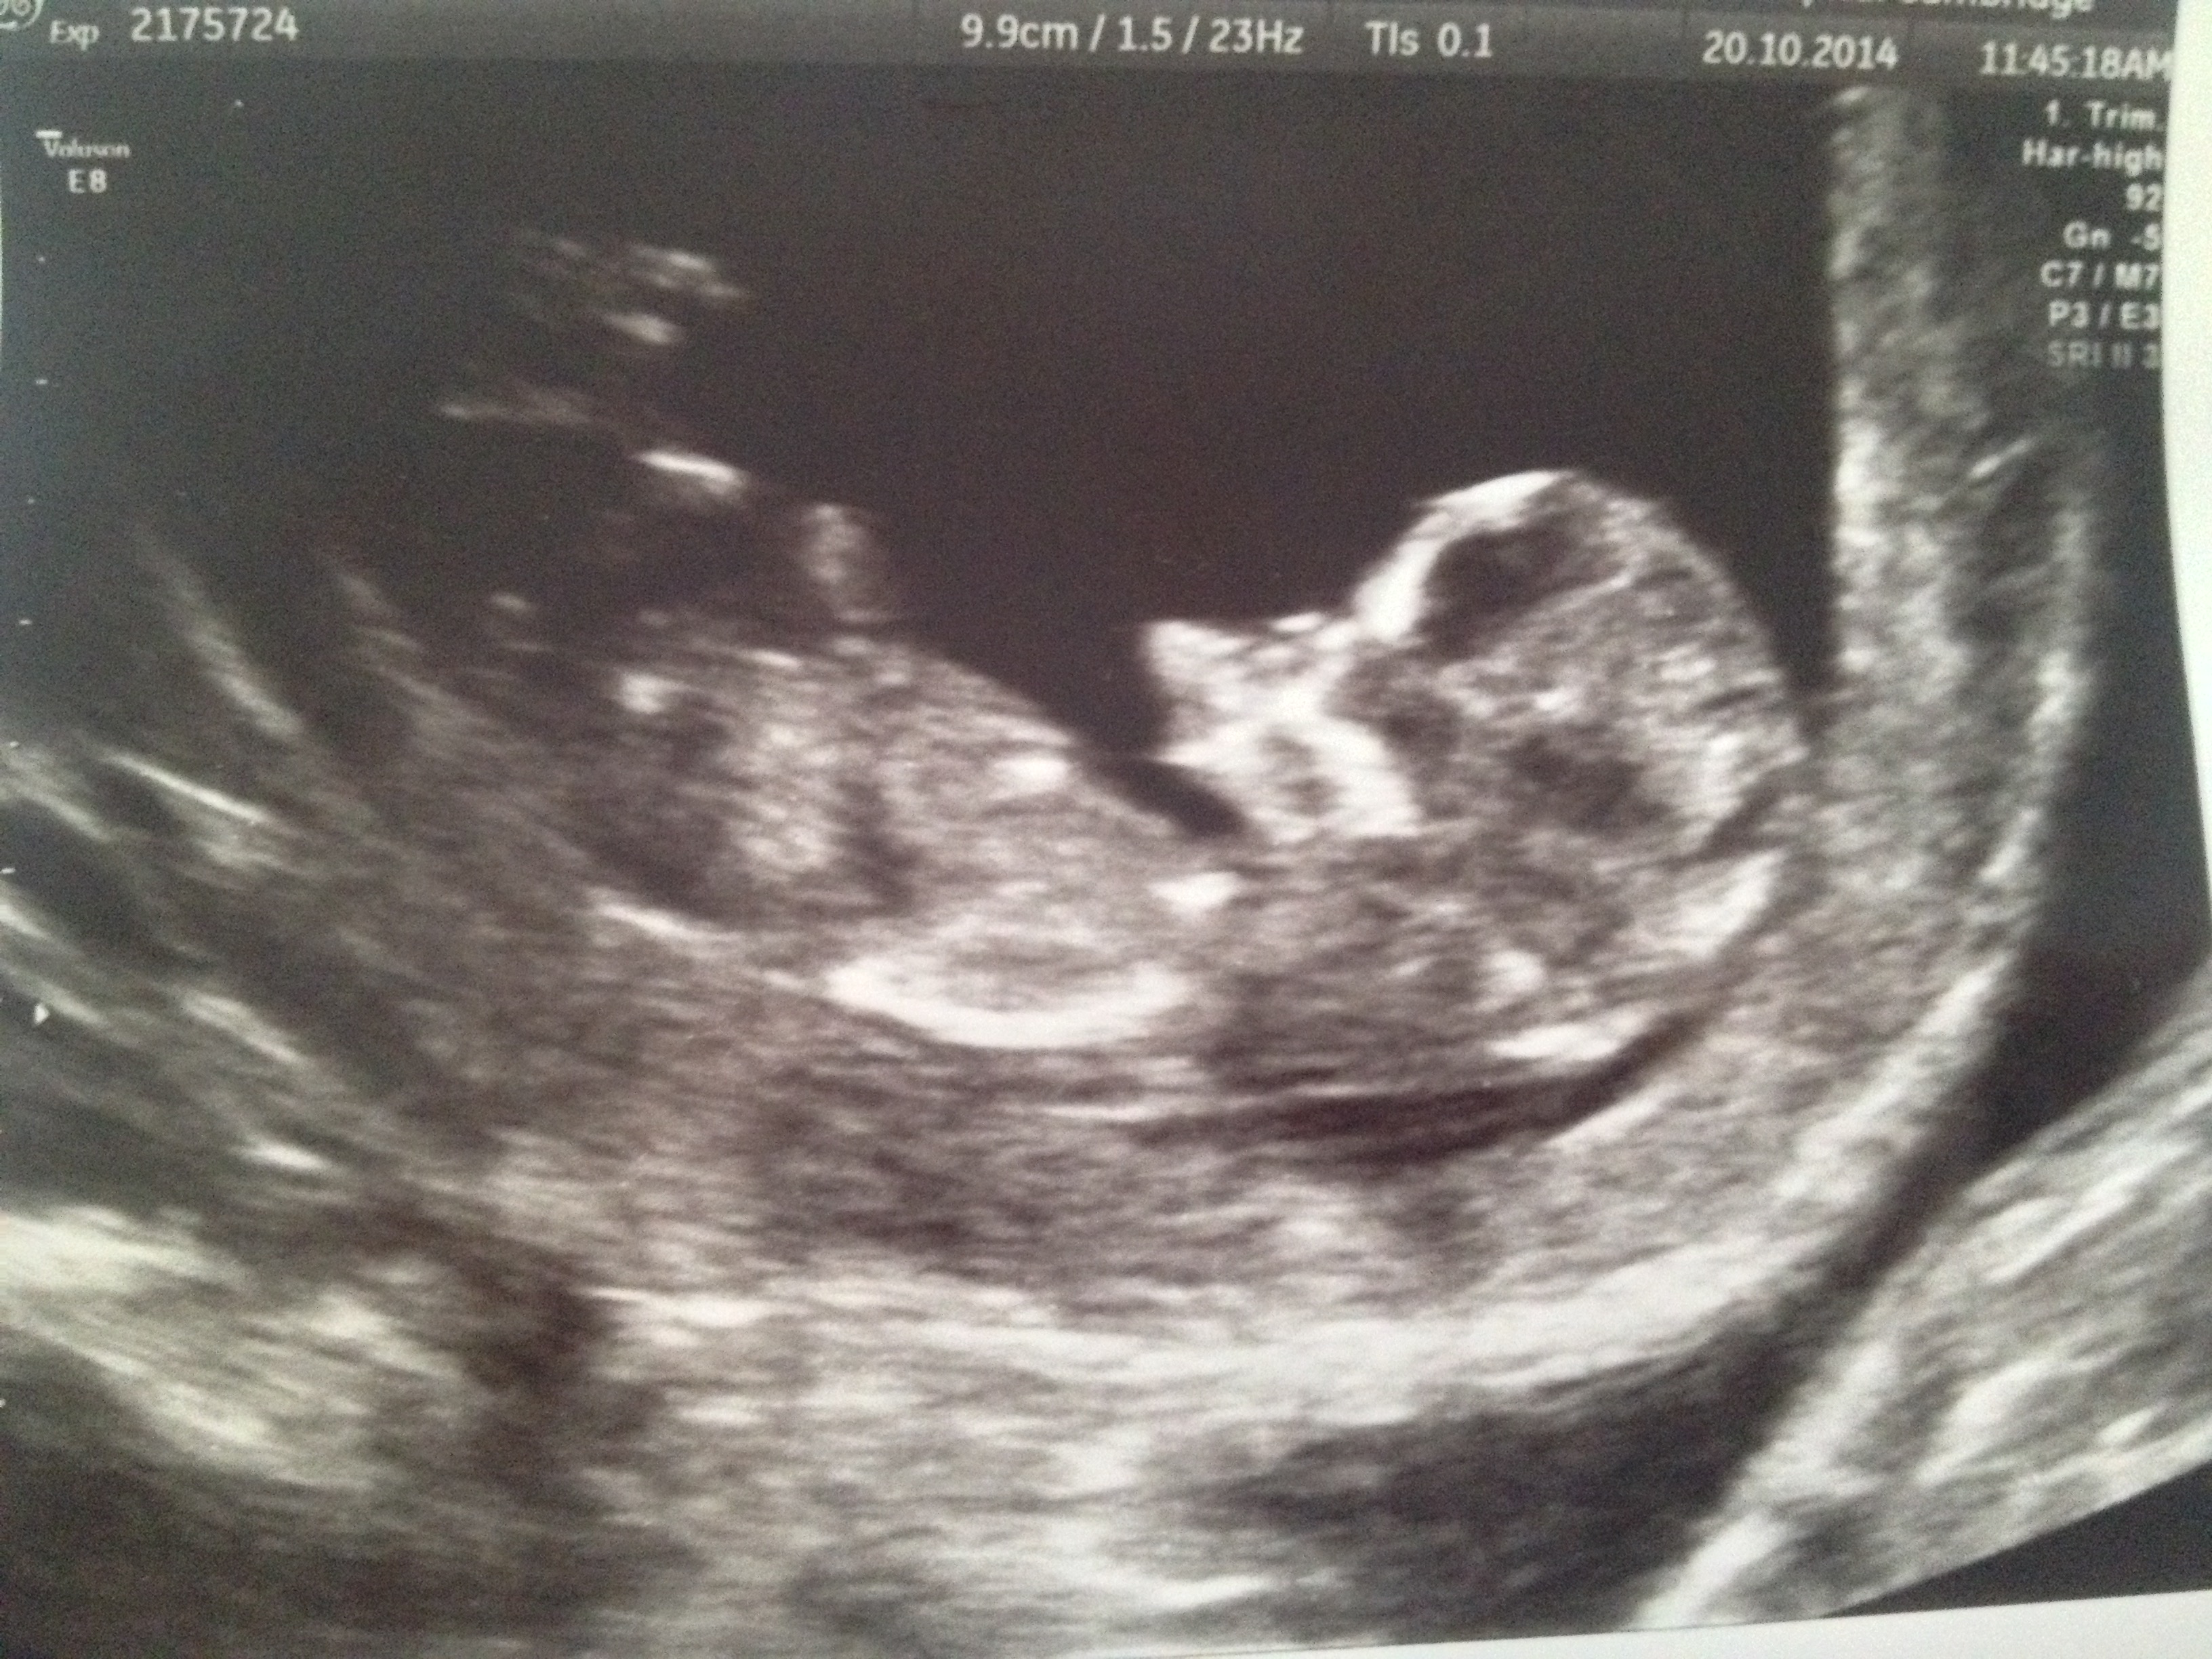

Any guesses? X

I think boy

Boy

blue

Boy guess

Baby boy!

Yes a boy, congrats! What are you hoping for?

Thanks everyone. Hoping for a boy. I find out tomorrow what i am having so will be sure to post here the results!! Blessings

Boy :)

Looks boyish to me too. Good luck!